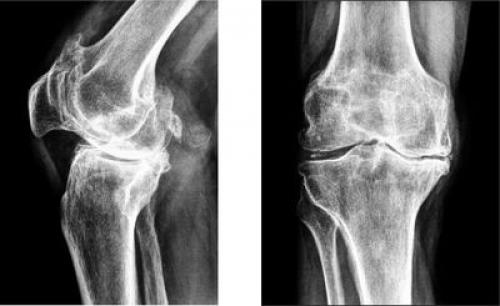

- гонартроз. Он встречается практически в 50% всех случаев поражения сочленения. Патология развивается очень долго. Среди симптомов этой болезни можно выделить такие: колено не болит в состоянии покоя, однако человеку становится трудно подниматься по лестнице, долго ходить, приседать и вставать с корточек. Во время движения больной слышит хруст в колене, у него снижается подвижность. Со временем, вследствие изнашивания хряща, расстояние между костными поверхностями уменьшается. При этом появляются остеофиты, нервы и сосуды сдавливаются, а само колено деформируется;

Гонартроз коленного сустава на рентгене.